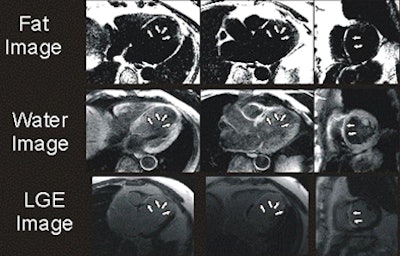

| Above, four-chamber, three-chamber, and short-axis images of a patient with fat deposition in segments of myocardial infarction. Precontrast fat-water separation imaging shows midwall fat deposition that is hyperintense in fat images and hypointense in water images. Late gadolinium-enhanced (LGE) infarct imaging shows an apical-septal chronic myocardial infarction. Below, fat-water separation imaging color overlay. Colored fat displayed on grayscale water images from two patients with chronic myocardial infarctions. Arrows point to midwall fat deposition. Images courtesy of Dr. James Goldfarb. |

The study examined 25 patients with LV MI (mean age, 64.3 years; range, 43.2-82.1 years) using a 1.5-tesla MRI scanner system. Protocols included volumetric cine, fat-sensitive, and late gadolinium-enhanced (LGE) infarct imaging. Water-fat separation was performed by using a three-point Dixon reconstruction from in- and opposed-phase black-blood gradient-echo images.

Fat deposition was seen in 68% of patients in areas of chronic MI. Patients with fat deposition on imaging had larger infarctions (30.0 mL ± 15.1 [standard deviation] versus 14.8 mL ± 6.1; p = 0.002), less wall thickening (2.3% ± 20.0 versus 37.8% ± 34.4; p = 0.003), and impaired endocardial wall motion (2.9 mm ± 2.0 versus 5.8 mm ± 2.6; p = 0.007) compared to normal patients, the group reported. In addition, the volume of fat deposition correlated with infarct volume, LV ejection fraction, LV end-diastolic volume index, and LV end-systolic volume index.

"Since fat deposition was found solely in myocardial segments with or directly adjacent to MI, one might infer that LV MI is a precursor to LV myocardial fat deposition," Goldfarb and his team wrote, adding that serial imaging over several years would be necessary to test the hypothesis. "We also found that fat deposition was predominately midmyocardial or midepicardial, whereas results of prior autopsy and CT studies suggest that fat deposition almost always affects the subendocardium."